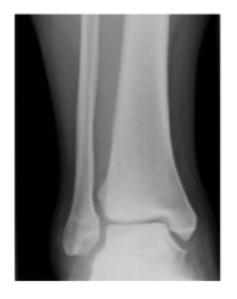

Ankle Specific Fractures

General Ankle Fracture

Diagnosis: Ankle fracture Mechanism: Twisting injury Common in: Old people